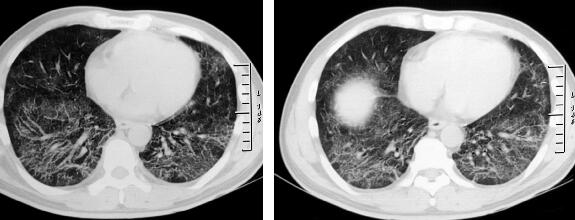

经莫西沙星治疗3天后体温稍降低,但仍可达38℃。双肺干鸣音较前增加,呼吸困难无缓解。此间实验检查结果:①血常规复查:白细胞计数7.16×109/L;中性粒细胞百分比67.9%;淋巴细胞百分比25.0%;②胸部X线检查(治疗一周后):双肺磨玻璃样影改变较前增多(图2);③无黑便,便常规:便隐血(+)。

图2

患者拟诊为CAP,经过治疗病情好转不明显,应该考虑两个问题:①是否为特殊病原体感染?②是否为非感染性疾病?根据患者的临床特点及胸部影像学为双肺广泛磨玻璃样影,应注意排除可能形成磨玻璃样影的疾病如病毒感染、过敏反应、风湿免疫性疾病肺累及、ANCA相关性血管炎等。患者黑便,应除外消化系统疾病:消化性溃疡、溃疡性结肠炎、肠结核、克罗恩病、消化系统肿瘤等,建议完善钡餐、胃镜及肠镜等相关检查,患者拒绝。因此,重新深入询问病史,并进行有针对性的检查非常重要。